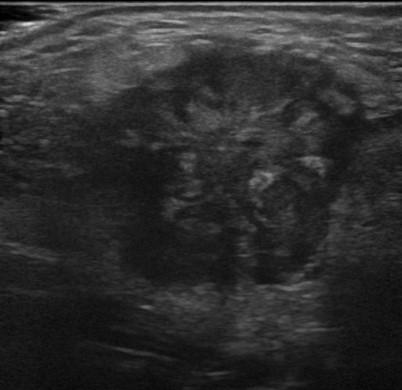

U tuyến nước bọt

» Thông tin: Nam giới – 83 tuổi.

» Lâm sàng: Khối vùng mang tai.

# Ung thư biểu mô tuyến (Adenocarcinoma).